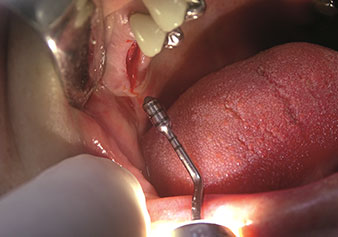

Situation following piezosurgical extraction

Fig. 2: Situation following piezosurgical extraction. Photo: © Dr Torsten Conrad (Bingen am Rhein)

One application, which is often underestimated is the atraumatic extraction of tooth roots or root fragments in the scope of alveolar management. The fine periotomes, which are currently available in two versions (EX1 and EX2 from W&H), can also be used to remove teeth which have previously undergone special endodontic treatment or ankylosed roots with ease. This results in extraction alveoli where both the hard and soft tissue are fully intact as it is generally possible to avoid reflection.

This establishes the optimal basis for subsequent or immediate implant treatment (Figures 1 and 2 included with the kind permission of Dr Torsten Conrad, Bingen a. Rhein).